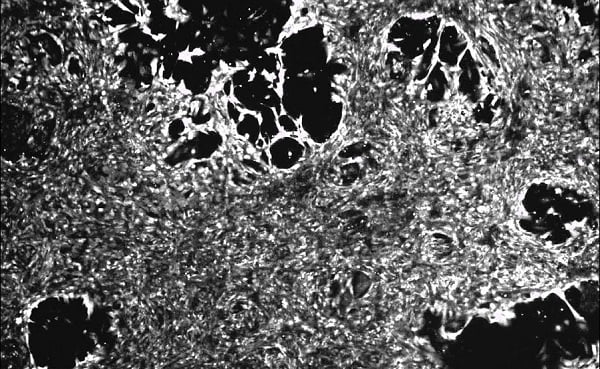

An article published by Phong and a team in the American Journal of Physiology-Cell Physiology discussed the primary culture of cardiomyocytes used tetramethylrhodamine methyl ester perchlorate (TMRM): a fluorescent stain that labels the mitochondria to enrich the cardiomyocytes. The cells that took up the stain at high amounts were cultured to establish viable neonatal rat cardiomyocyte. The cells could maintain spontaneous contractility and display responses to chronotropic agents (showing the expression of functional adrenergic and muscarinic receptors) and calcium cycling.